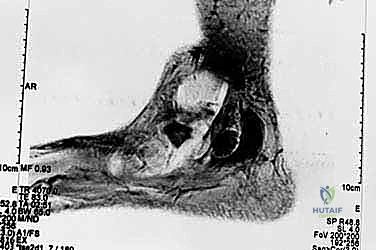

- التصوير بالرنين المغناطيسي للأعصاب (MR Neurography):

- في الحالات المعقدة، يوفر صورًا ثلاثية الأبعاد مفصلة للأنسجة الرخوة، مما يساعد في التخطيط الجراحي الدقيق وتحديد حجم النسيج الندبي.